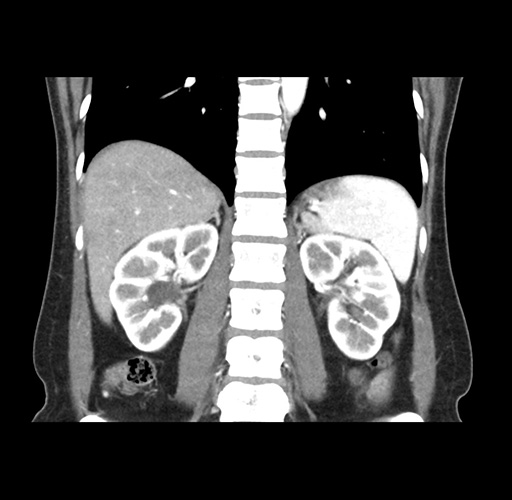

Imaging Analysis

Look through the patient's CT scan to identify any areas of concern for the necessary procedure.

Based on your CT findings, which issue(s) would give reason for "planned slowing down moment(s)" in this case?